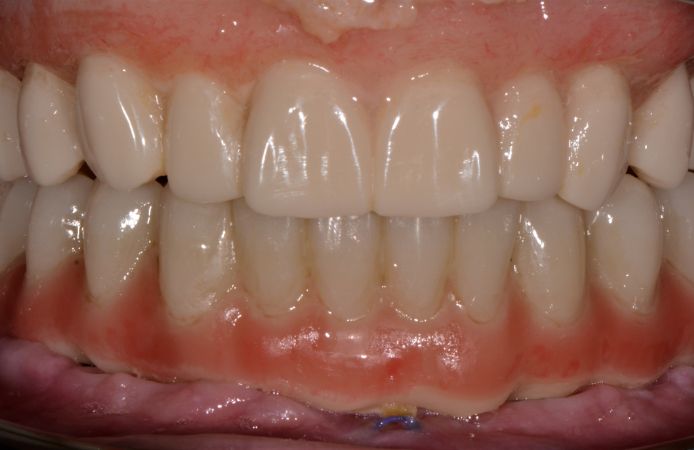

Figure 2.